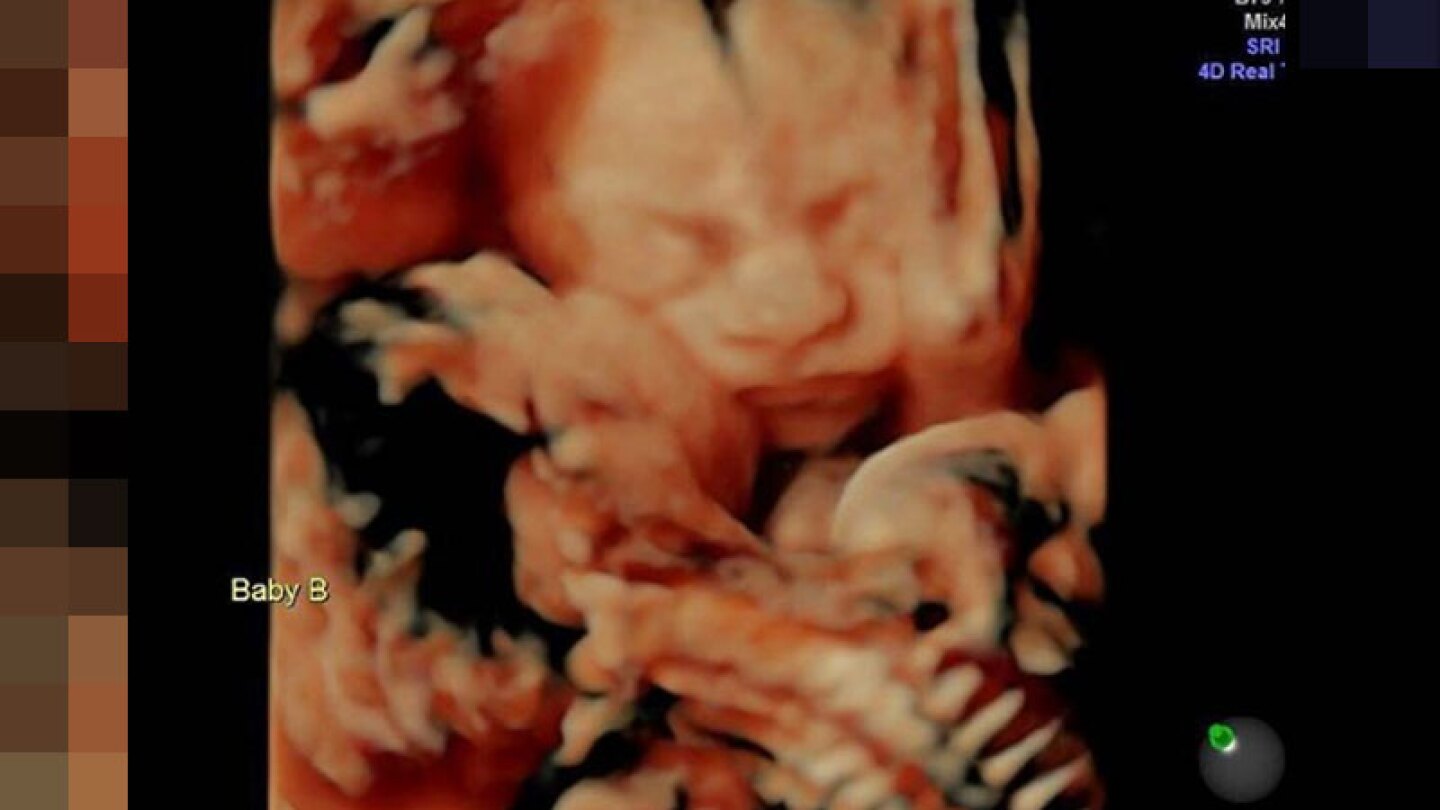

/Se ha comprobado de diferentes formas que los hermanos gemelos tienen una conexión especial y estas dos gemelas son una prueba de ello, aunque siguen en el vientre de su madre pareciera que ya se tienen una amor incondicional y puro. Esta puede ser la foto más tierna del mundo de un ultrasonido.

Carissa Grill acudió junto a su pareja Randy a una clínica especializada en ecografías en 4D, esto en Pensilvania y es que la mujer tiene 25 semanas de embarazo y quiso verificar que todo estuviera en orden, su sorpresa fue doble ya que se enteró que estaba esperando a dos lindas niñas y dicha noticia vino acompañada de un conmovedor ultrasonido en donde se puede observar como una de las pequeñas le está dando un tierno beso a su hermana.

[comments] Isabella le está dando a su hermanita Callie un beso en la mejilla. Estoy sorprendida por el amor y el apoyo que he recibido por estos dos hermosos bebés y el ultrasonido que compartí con todos ustedes… gracias a todos los que enviaron amor. En otras noticias, tengo 25 semanas y estoy muy ansiosa y emocionada de conocer a mis dos pequeñas bebés”, escribió en otra publicación la orgullosa madre. [/comments]